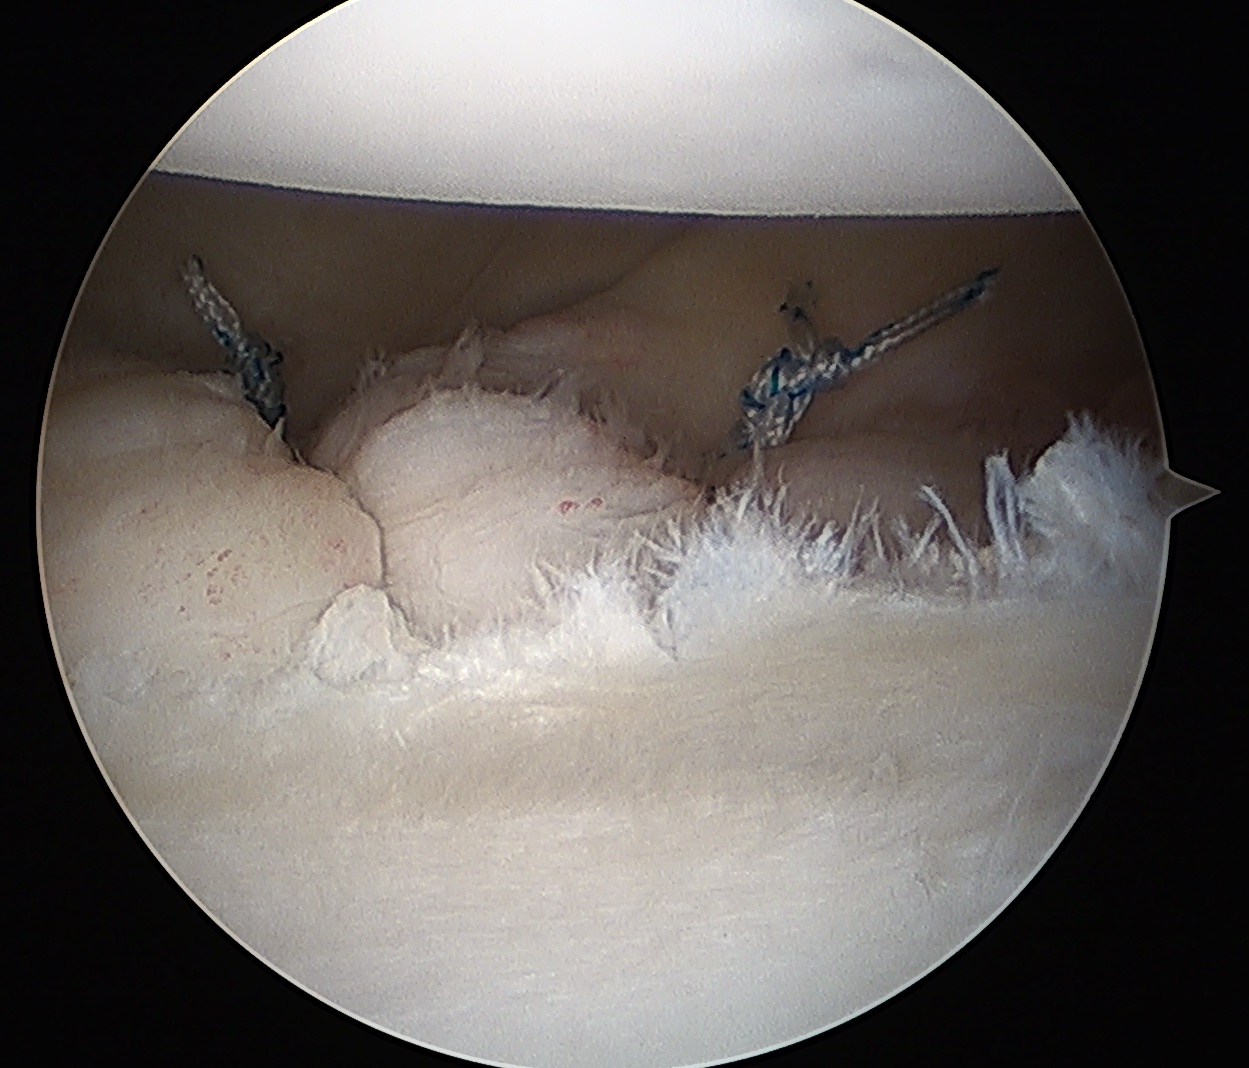

Technique arthroscopic anterior labral / Bankart repair

Steps

Debride anterior glenoid bone to bleeding bone

Insert anchors

Inferior anchor at 5.30 o'clock

- curved anchor guide / trans-subscapularis

- on rim of glenoid

Other anchors typically at 3 and 4 o'clock

Pass sutures and tie knots

Typically curved suture passers

Aim to tighten capsule medially and superiorly onto glenoid